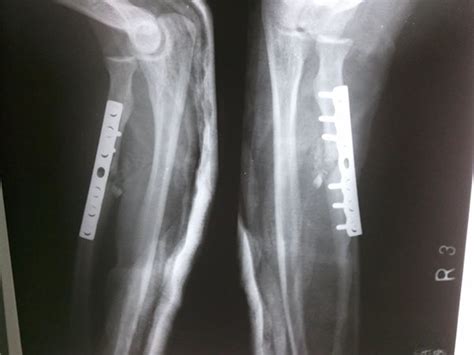

The radial head is forced into the capitulum of humerus the proximal shaft of ulna is fractured, and the head of the radius dislocates anteriorly at the elbow. Presence of associated fractures portends a poor. Commonly caused from foosh this can be accompanied by dislocation of the radius and/or ulna which can complicate the management of this injury. An isolated ulna fracture may be associated with dislocation of the radial 9. A few patients have axillary nerve damage (reducing sensation over the middle deltoid) or axillary artery damage. It is recommended that displacement be measured as the angle between a line perpendicular to the articular surface with another down the shaft of the proximal. These injuries usually occur from either a direct blow to the forearm or a fall on outstretched hands (foosh). Jagdeep singh1, *, anoop kalia2, anshul dahuja1. 1 department of orthopaedics, guru gobind singh medical college and hospital, faridkot, punjab, india. Application of the plate to the proximal bone when using a dorsal plate requires elevation and. They are often associated with other injuries including olecranon fractures, elbow dislocations, medial epicondyle fractures and ulna shaft fractures. Isolated radial shaft fractures are uncommon but can occur from projectile injury such as a gunshot blast. The anatomic midshaft forearm plating system offers a variety of plates that can be used to treat fractures, fusions, and osteotomies of the radius and ulna. Dislocation and angulation are usually described. The proximal radius consists of the radial head, neck and tuberosity. The radial head is forced into the capitulum of humerus the proximal shaft of ulna is fractured, and the head of the radius dislocates anteriorly at the elbow. Galeazzi fractures (radial midshaft fractures with distal radioulnar joint druj instability) account for 7 percent of all forearm fractures.